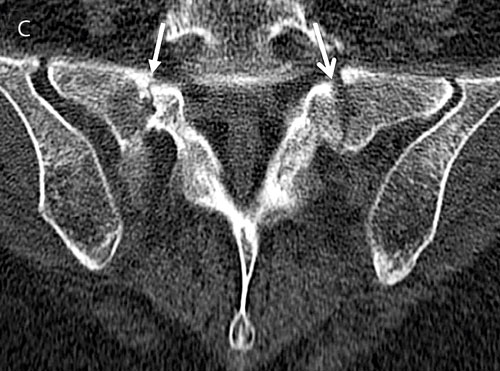

Figur 2. En 65-årig kvinna som behandlades med högdos kortikosteroider för polymyalgia rheumatica hade sedan 2 veckor fått tilltagande smärtor i ländryggen. Smärtorna strålade ned i båda benen, och hon hade mycket svårt att gå. I övrigt inga neurologiska fynd. Röntgen ländrygg (A) visade ingen kotkompression, utan endast degenerativa förändringar. Patienten fick accentuerande smärtor som krävde inläggning 1 vecka senare. MRT ländryggsöversikt (B) utfördes. Denna visade högsignalerande områden (pilar) bilateralt i sakrum förenliga med insufficiensfraktur, vilken också kunde verifieras med datortomografi (C).